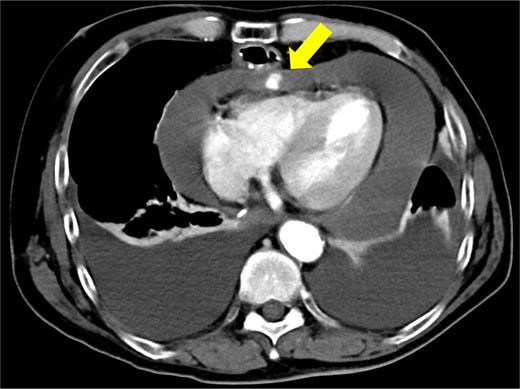

The patient underwent robotic subtotal esophagectomy, two-region lymph node dissection, narrow gastric tube was created by hand assisted laparoscopy and cervical anastomosis was performed via the retrosternal route. The operation took 613 min, with minimal blood loss. The retrosternal route under camera assist was created without bleeding, and no intraoperative hemodynamic changes or complications were observed. The pathological stage was pT1b(SM2)pN1M0 pStage II (Japanese Classification of Esophageal Cancer, 12th Edition). Esophageal fluoroscopy on postoperative day (POD) 7 showed a minor leak at the anastomotic site, which improved by POD 14 after cervical wound release and drainage. The minor leak at the anastomosis site has been the cause of prolonged hospital stay. The patient experienced sudden intermittent chest pain on POD 17, but his vital signs remained stable. Echocardiography revealed an increased amount of pericardial fluid. He was diagnosed with pericarditis and prescribed colchicine by cardiologist; however, pericardial fluid levels continued to increase. Pericardiocentesis with pericardial catheter insertion was performed on POD 34, revealing bloody pericardial fluid. Blood drainage persisted at approximately 300 ml/h. Urgent contrast-enhanced CT revealed contrast extravasation from the anterior right ventricle (Fig. 2). Coronary angiography revealed aneurysmal changes in the peripheral right ventricular branch without apparent hemorrhage (Fig. 3).

Coronary angiography reveals aneurysmal changes in the right ventricular branch without evident bleeding (arrow).